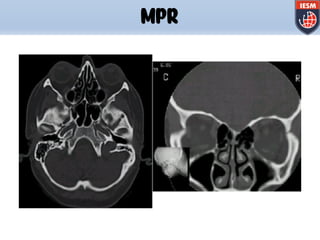

MPR